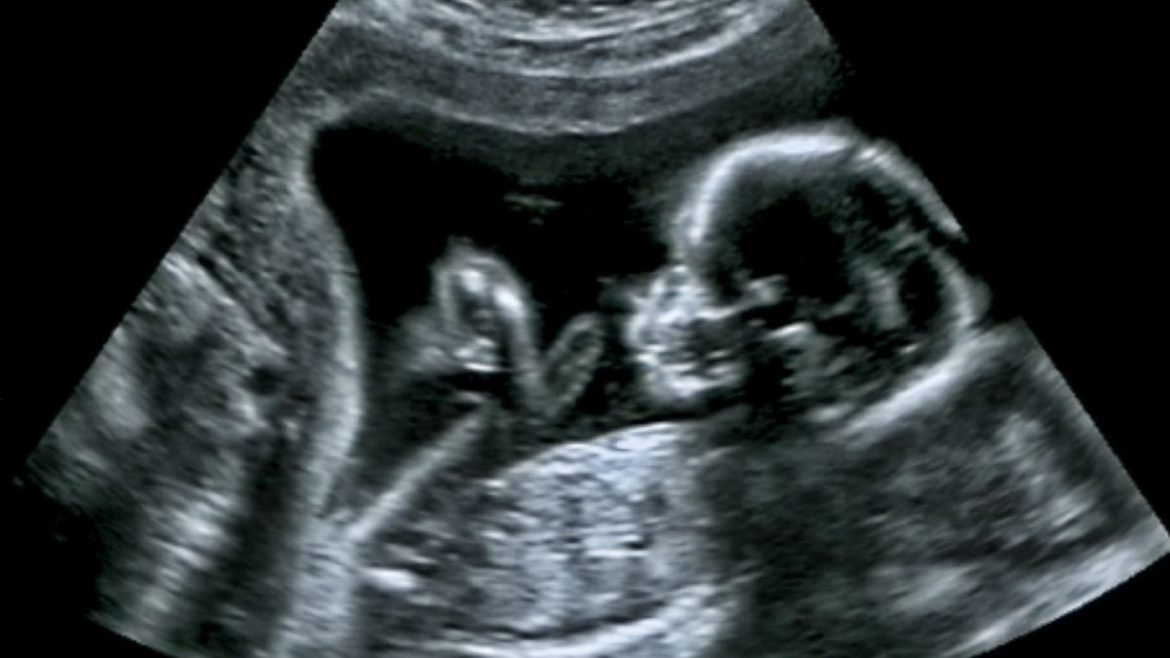

Προς το τέλος του έβδομου μήνα της εγκυμοσύνης εντοπίστηκε ο όγκος (σύνδρομο Κάσαμπακ-Μέριτ)στο έμβρυο, σε μια μαιευτική κλινική της Μιλούζ, στην ανατολική Γαλλία. Λόγω του όγκου στο ύψος του λαιμού, υπήρχε κίνδυνος να κλείσει ο αεραγωγός και να πεθάνει το μωρό πριν από τη γέννησή του, εξήγησε ο γιατρός Κρις Μινέλα, του Κέντρου Προγεννητικής Διάγνωσης των Πανεπιστημιακών Νοσοκομείων του Στρασβούργου, σε συνέντευξη Τύπου που παραχώρησε στο νοσοκομείο «Γυναίκα-Μητέρα-Παιδί» της Μιλούζ.

Ο όγκος μεγάλωνε πολύ γρήγορα και είχε καλύψει όλη τη βάση του προσώπου του εμβρύου. Μετά τη διάγνωση, το Κέντρο Αναφοράς των Αγγειακών Επιδερμικών Ανωμαλιών των Δημόσιων Νοσοκομείων της Λιόν, που ειδικεύεται στις σπάνιες νόσους, πρότεινε να χορηγηθεί στο έμβρυο, πριν από τη γέννησή του, ένας αντιαγγειογενετικός παράγοντας (το φάρμακο Sirolimus, που περιορίζει την ανάπτυξη αγγείων), υπό την επίβλεψη του καθηγητή Λοράν Γκιμπό.